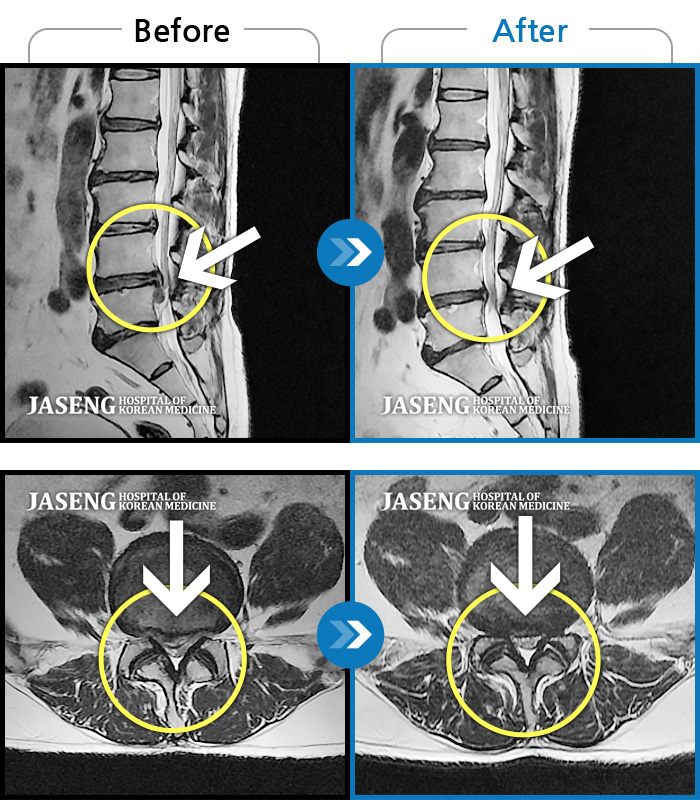

MRI 치료사례

허리 및 우측 하지 통증